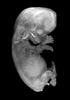

Carnegie Stage 23 (56 post-ovulatory days)

Most embryos at stage 23 are approximately 56-57 postovulatory days old and measure 23-32 mm in length. Distinguishing criteria for this stage include fusion of the eyelids at the medial and lateral margins, clear distinction of the subdivisions of the upper and lower limbs, the forearms appear at or above the level of the shoulders, the superficial vascular plexus of the head is very close to the vertex, and the external genitalia are well developed but not always sufficiently to distinguish the embryo's sex.

(NOTE: These specimens are late stage 23.)